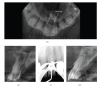

Cone Beam Computed Tomography (CBCT) is a diagnostic imaging modality that provides high-quality, accurate three-dimensional (3D) representations of the osseous elements of the maxillofacial skeleton. CBCT systems are available that provide small field of view images at low dose with sufficient spatial resolution for applications in endodontic diagnosis, treatment guidance, and posttreatment evaluation. This article provides a literature review and pictorial demonstration of CBCT as an imaging adjunct for endodontics.